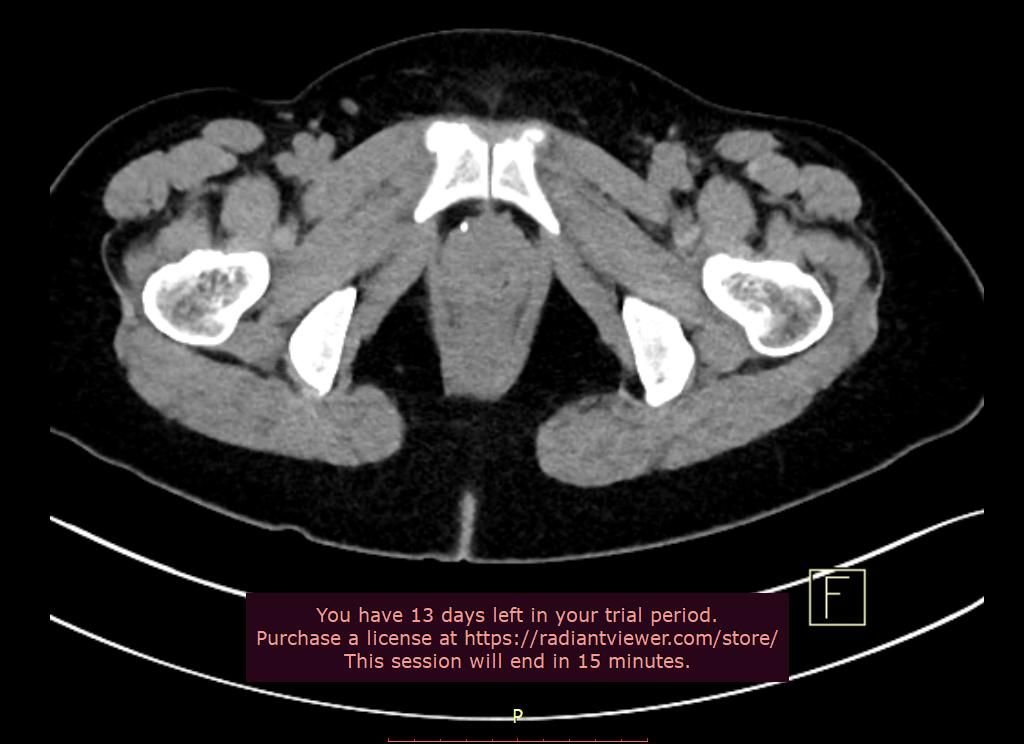

아래 사진 캡처해서 업로드해보았는데요. 오른쪽에 하얀 점 1개, 왼쪽에 위아래로 하얀 점 2개가 보이는데요.

결석 제거 후에 찍은 거라서 결석은 아닌 것 같은데요.

이건 무슨 석회화라고 봐야 할까요? 아니면 ct 음영 때문에 보이는 걸까요?

위치로 봐서는 자궁이나 질과 같은 생식기 벽에 양성 석회회가 있는 것 같습니다.

특별한 문제가 되거나 별도의 처치가 필요한 것은 아니구요

CT 아티팩트는 아닐 것 같습니다